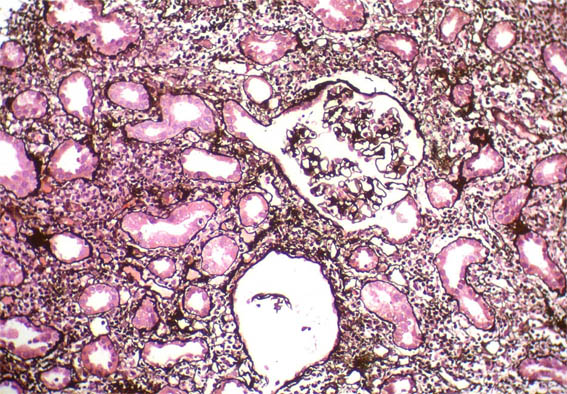

Figure 10. Methenamine-silver staining, X200.